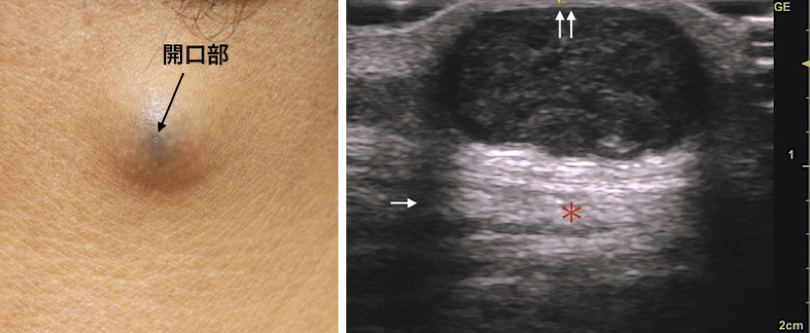

*粉瘤腫(アテローマ、epidermal cyst)とは?

その中で、表皮嚢腫(粉瘤、アテローマ)のくりぬき法を紹介します。皮膚外科特有の手技で、4mmの穴から倍以上の大きさのできものを取り出します。

局所麻酔後にトレパンで4mmの穴をあけます。何故か3mmではうまくいかないんです。

次に腫瘤をつまみ、一気に中身を押し出します。4mmの穴から、1cm以上のできもが排出されました。

取り残しがないか、肉眼的に十分に確認します。取り残しがあると再発しますからね。穴はこのままでも自然に閉じますが、このケースでは縫合した方がきれいですね。

数ヶ月もすると、ほとんどわからない傷になっているでしょう。最後に病理検査を行い、嚢腫壁が完全に摘出されていることを顕微鏡的に確認することが大切です。高齢者の場合は、まれに癌化していることもありそのチェックも必要です。